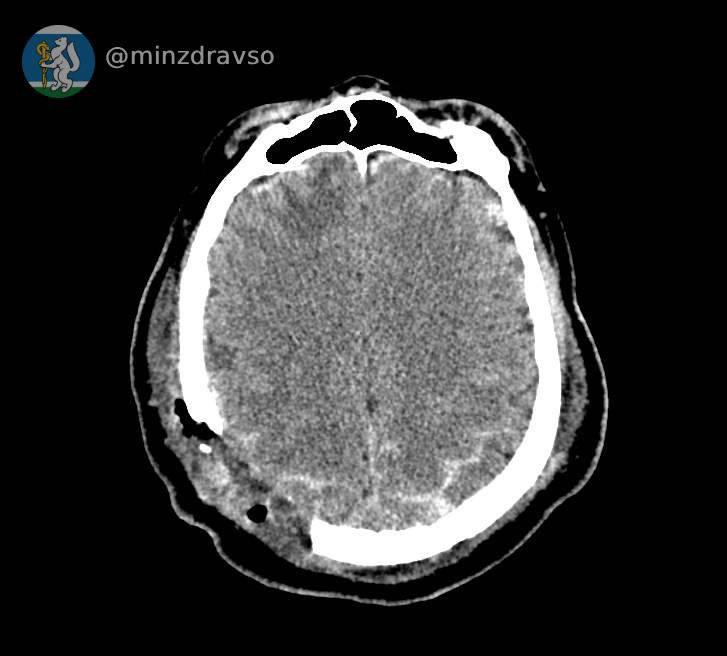

На Урале стрела башенного крана пробила дыру в черепе мужчины.На Урале стрела башенного крана пробила дыру в черепе мужчины.04 Сентября 2025

Спасать его пришлось врачам из трёх городов.

Трагедия произошла в Серове. 57-летний мужчина поступил в стационар скорой помощи в критическом состоянии: стрела строительного крана расколола ему череп. Врачи быстро сделали томографию и нашли обломки костей. Самый острый из них мог в любой момент убить пациента. После анализов серовские врачи проконсультировались с коллегами из Екатеринбурга и приняли решение оперировать мужчину в Нижнем Тагиле. Когда пациента доставили в больницу, его уже ждала операционная бригада. Медики удалили отломки костей, гематомы, восстановили целостность твёрдой мозговой оболочки. Кто обитает на дне океана?Кто обитает на дне океана?22 Июня 2023